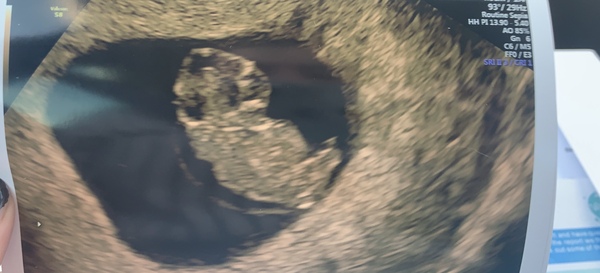

Aww @Workingmama1 I’m so pleased for you and glad you feel better after a scan, I’ve also had mine today and it went amazing after bursting out crying as soon as the sonographer put the screen on I could see it was a growing baby shaped bean with a perfect heart rate. I’m so over the moon right now hopefully we can relax now and we know our little cramps are normal!! I am measuring 8 wk 3 🤩